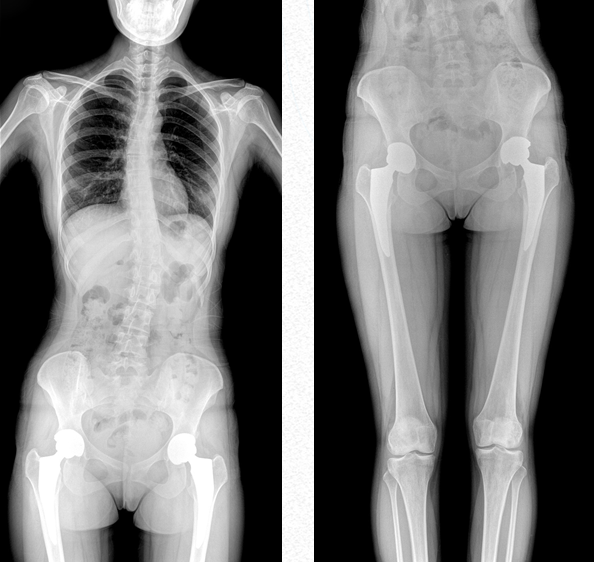

作為醫(yī)療機(jī)構(gòu)普放的多功能診斷需求進(jìn)行專(zhuān)業(yè)設(shè)計(jì)的新一代智能影像設(shè)備,普愛(ài)醫(yī)療PLX8600是一款超大視野多功能平板動(dòng)態(tài)DR,17*34英寸動(dòng)態(tài)平板,整板拍攝不拼接,呈現(xiàn)更準(zhǔn)確的長(zhǎng)骨影像。它在真正意義上實(shí)現(xiàn)了多科室、多功能應(yīng)用,如各類(lèi)常規(guī)的X線檢查、消化道檢查、骨科檢查、婦科、兒科檢查等。

超大視野范圍,一次成像不拼接,減少拍片次數(shù),縮短拍攝時(shí)間,降低患者的輻射劑量吸收

全脊柱成像

用于全脊柱攝影,為臨床提供準(zhǔn)確的二維影像,支持全脊柱斜位透視診斷,方便對(duì)椎弓根峽部進(jìn)行觀察,診斷腰椎是否滑脫。如:先天性脊柱側(cè)彎、后凸畸形、多節(jié)脊柱創(chuàng)傷等。此外,大視野動(dòng)態(tài)透視功能,在全脊柱脊髓造影的臨床應(yīng)用中也頗具優(yōu)勢(shì)。

雙下肢成像

用于創(chuàng)傷弓|起的四肢骨折,進(jìn)行較長(zhǎng)髓內(nèi)釘術(shù)前診斷、術(shù)后復(fù)診的大視野攝影。

PLX8600大視野動(dòng)態(tài)平板DR可攝影、可透視、可造影,臨床適用范圍廣泛,滿足臨床拍攝需求。與市面常規(guī)多張攝影再軟件拼接的DR相比,PLX8600大視野動(dòng)態(tài)平板DR解決了拼接圖像存在密度不均勻,拼接處圖像配準(zhǔn)和放大效應(yīng)等問(wèn)題,一體式的機(jī)架,擺位簡(jiǎn)單快捷 ,具有畸變率低、測(cè)量精度高、圖像質(zhì)量好、無(wú)拼接痕跡等優(yōu)點(diǎn)。這款DR不僅融合了市面上17*17英寸動(dòng)態(tài)DR的功能,除此之外它獨(dú)具特色的17*34英寸超大動(dòng)態(tài)視野范圍,給臨床應(yīng)用帶來(lái)較高價(jià)值,減輕醫(yī)院設(shè)備投入成本,獲得更大收益。